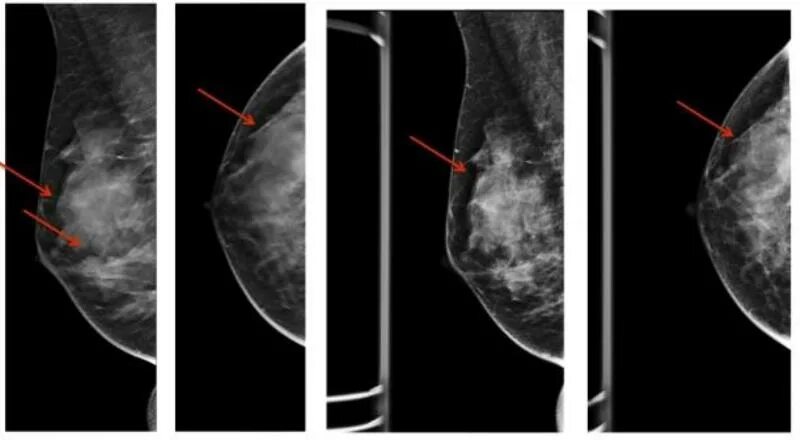

Диффузная мастопатия с преобладанием фиброзного